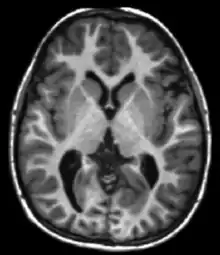

Due to the availability of dense 3D measurements via technologies such as magnetic resonance imaging (MRI), computational anatomy has emerged as a subfield of medical imaging and bioengineering for extracting anatomical coordinate systems at the morphome scale in 3D. The spirit of this discipline shares strong overlap with areas such as computer vision and kinematics of rigid bodies, where objects are studied by analysing the groups responsible for the movement in question. Computational anatomy departs from computer vision with its focus on rigid motions, as the infinite-dimensional diffeomorphism group is central to the analysis of Biological shapes. It is a branch of the image analysis and pattern theory school at Brown University[10] pioneered by Ulf Grenander. In Grenander's general metric pattern theory, making spaces of patterns into a metric space is one of the fundamental operations since being able to cluster and recognize anatomical configurations often requires a metric of close and far between shapes. The diffeomorphometry metric[11] of computational anatomy measures how far two diffeomorphic changes of coordinates are from each other, which in turn induces a metric on the shapes and images indexed to them. The models of metric pattern theory,[12][13] in particular group action on the orbit of shapes and forms is a central tool to the formal definitions in computational anatomy.

Computational anatomy is the study of shape and form at the morphome or gross anatomy millimeter, or morphology scale, focusing on the study of sub-manifolds of points, curves surfaces and subvolumes of human anatomy. An early modern computational neuro-anatomist was David Van Essen[14] performing some of the early physical unfoldings of the human brain based on printing of a human cortex and cutting. Jean Talairach's publication of Talairach coordinates is an important milestone at the morphome scale demonstrating the fundamental basis of local coordinate systems in studying neuroanatomy and therefore the clear link to charts of differential geometry. Concurrently, virtual mapping in computational anatomy across high resolution dense image coordinates was already happening in Ruzena Bajcy's[15] and Fred Bookstein's[16] earliest developments based on computed axial tomography and magnetic resonance imagery. The earliest introduction of the use of flows of diffeomorphisms for transformation of coordinate systems in image analysis and medical imaging was by Christensen, Joshi, Miller, and Rabbitt.[17][18][19]

The central objects are shapes or forms in computational anatomy, one set of examples being the 0,1,2,3-dimensional submanifolds of , a second set of examples being images generated via medical imaging such as via magnetic resonance imaging (MRI) and functional magnetic resonance imaging.